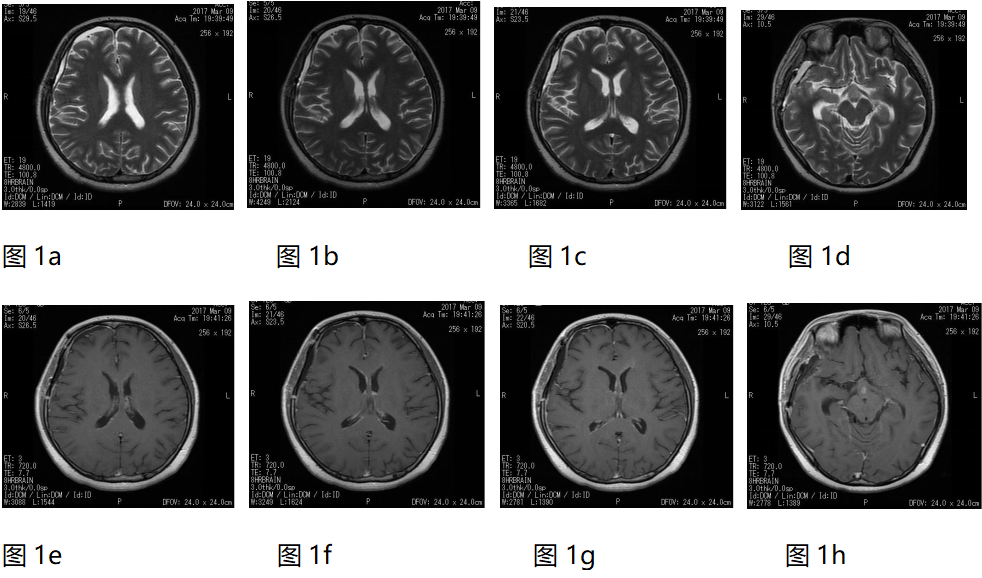

图1. TMZ标准放化疗与联合DDP的治疗方案